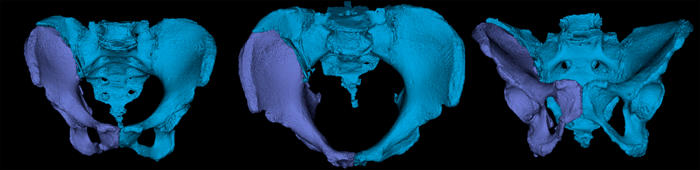

术前CT三维重建

人工智能手术规划